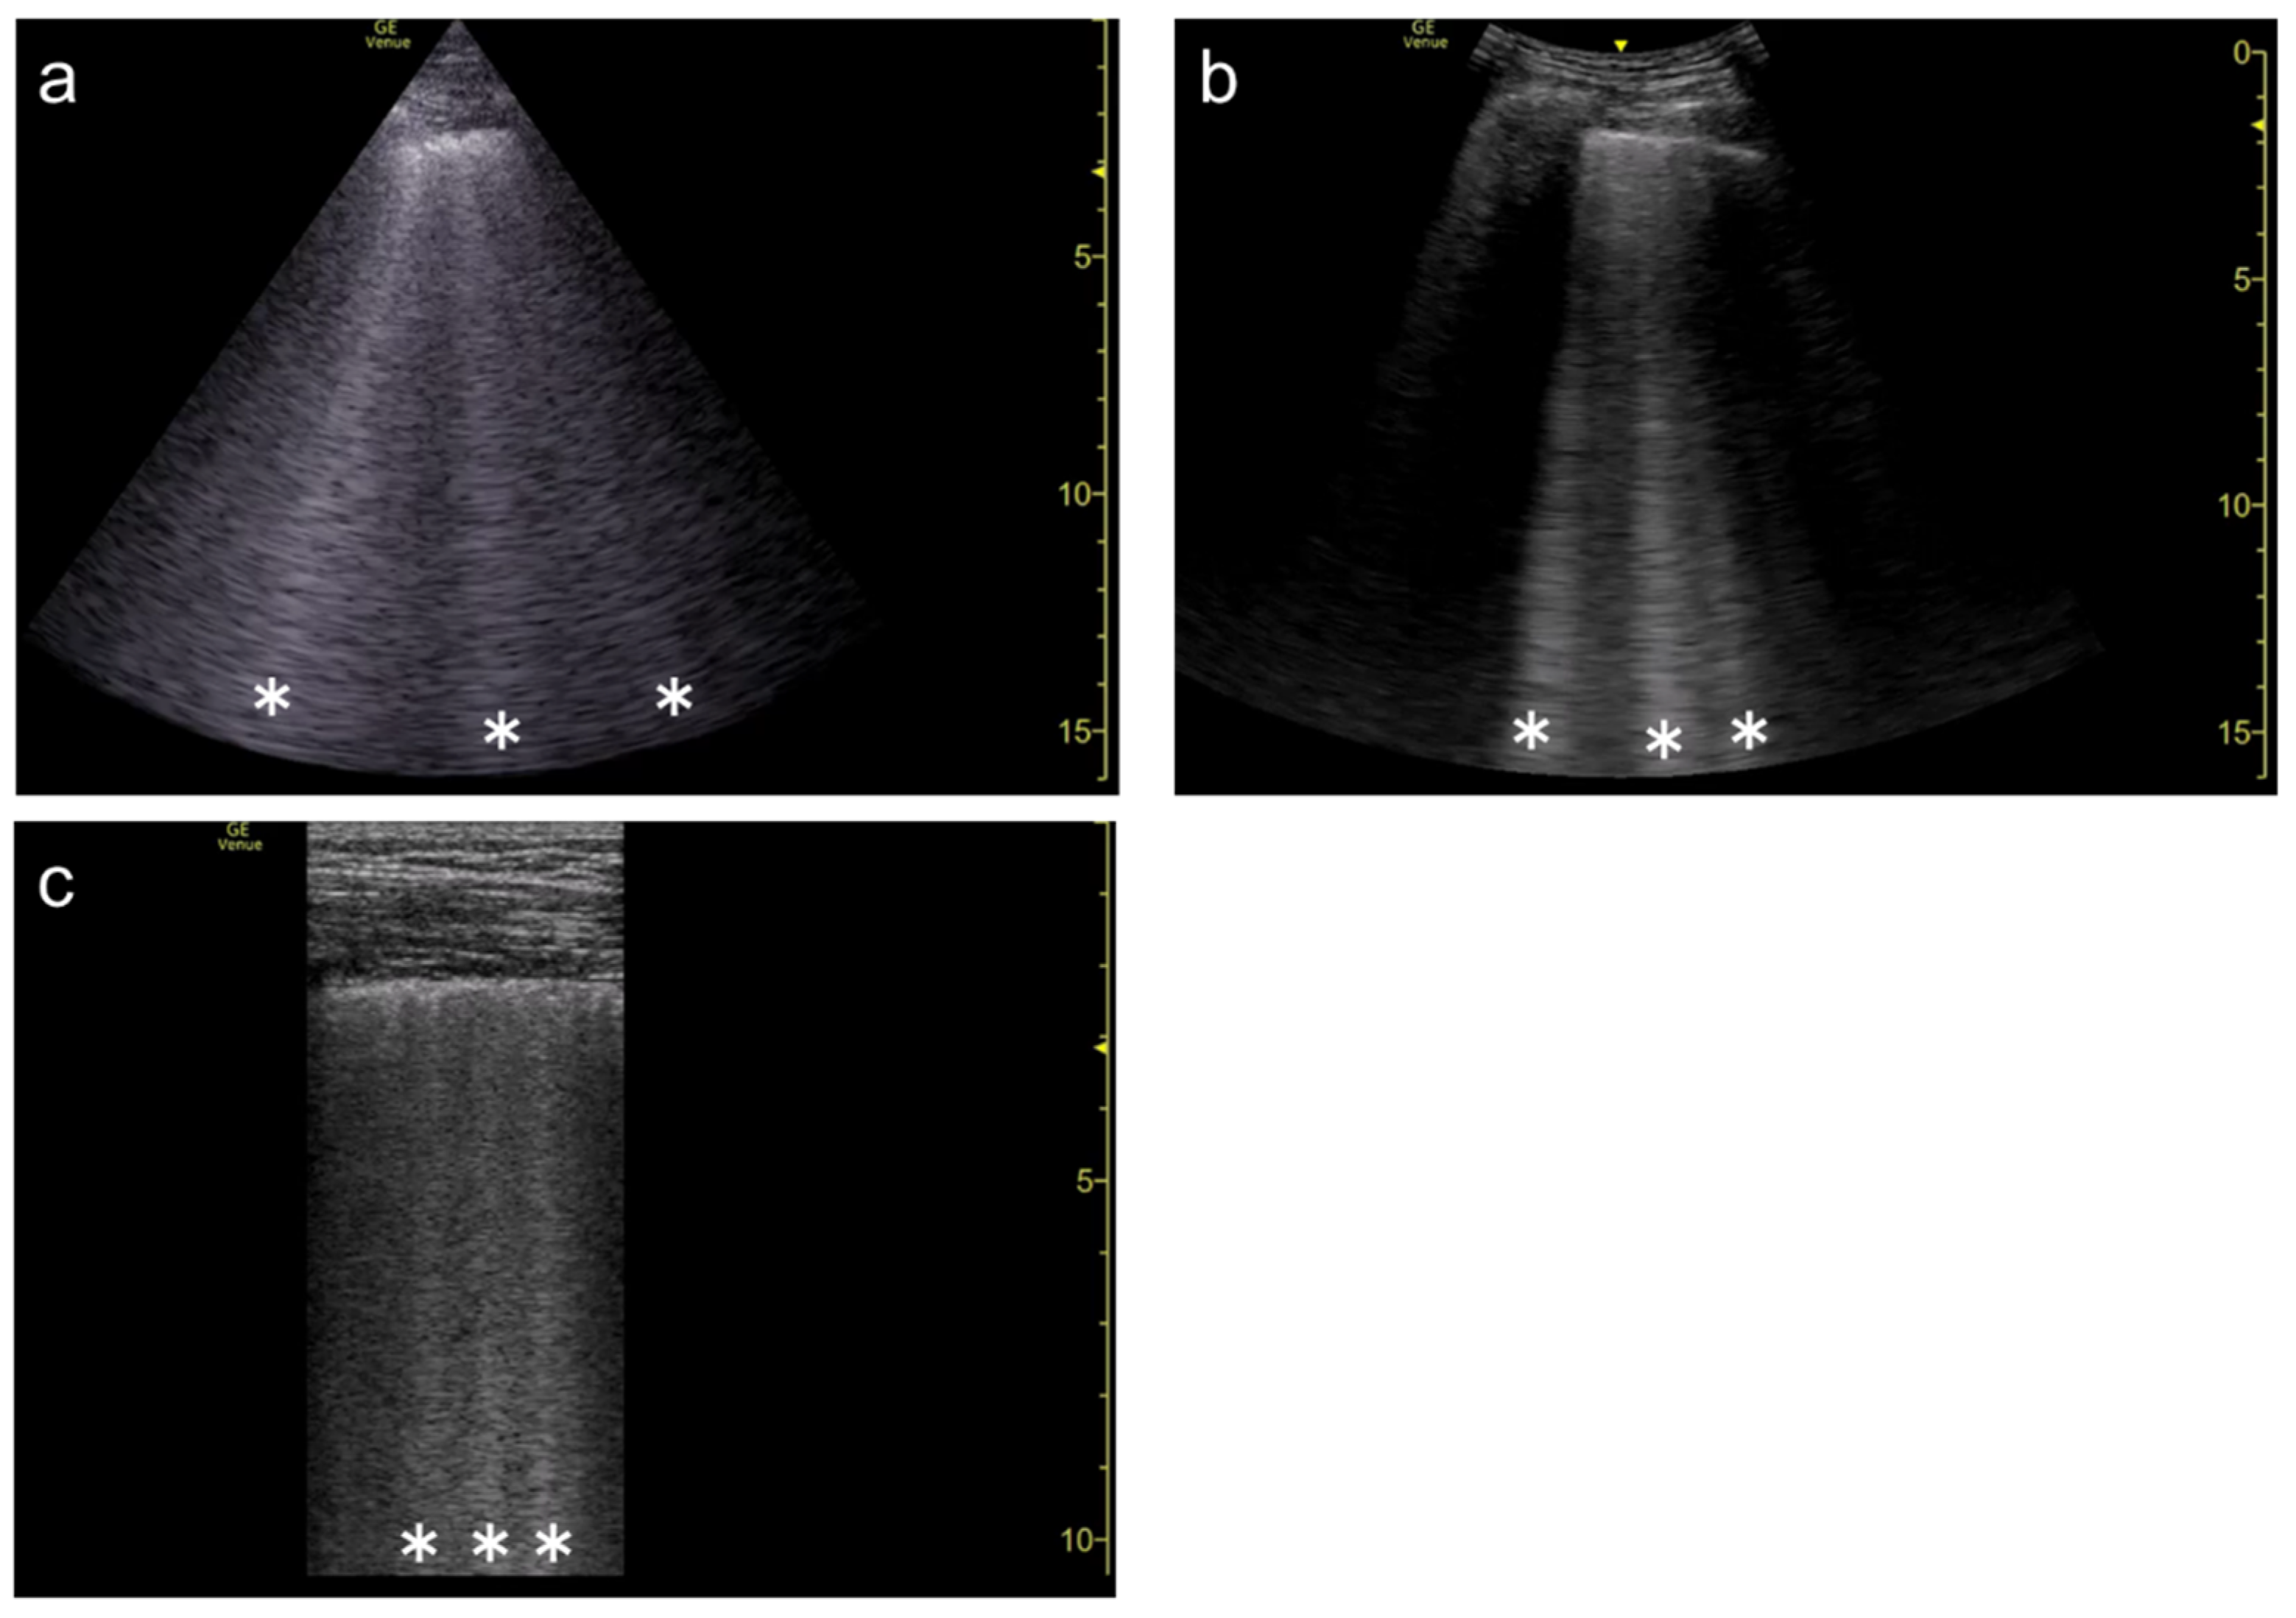

2. Generation of Vertical Artifacts

2.2. The Theory of Acoustic Trap

2.3. Our Basic Research Supporting the Theory

3.1. Spatial Compound Imaging

3.2. Focal Point

3.3. Frequency

3.4. Selection of Transducers